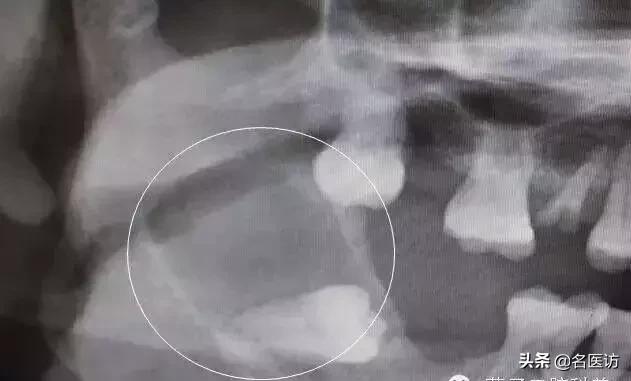

当这些智齿突破牙龈,它们便被称为“萌出”。如果智齿不能萌出,或只能部分萌出牙龈,就叫做“阻生”。

阻生智齿很常见,一般来说是不痛的。需要注意的是,无论智齿是否萌出,如果不认真使用牙刷、牙线清洁牙齿,没有定期看牙医的话,智齿可能会引起问题,比如肿痛等。